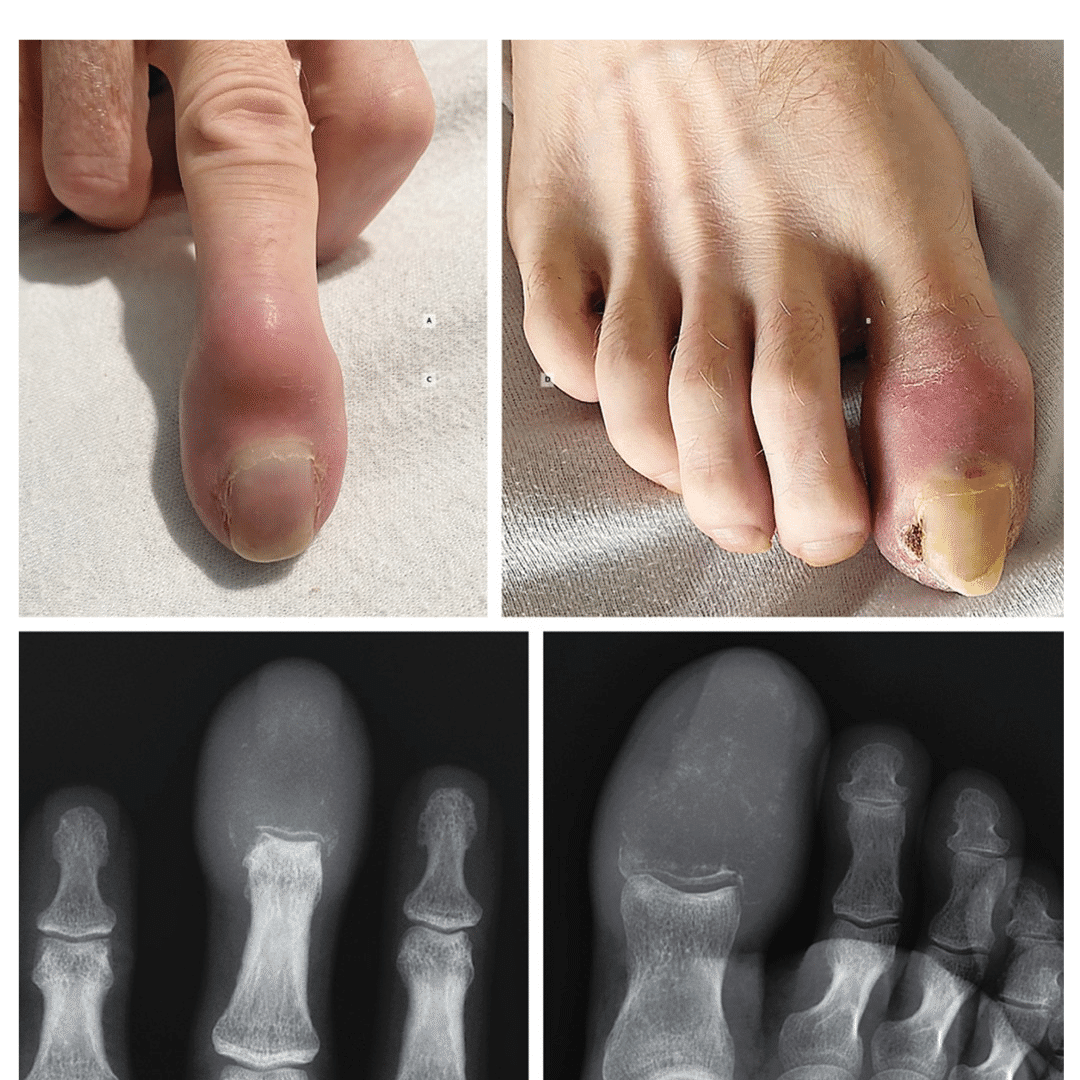

Avustralya’da gerçekleşen vakada, hasta, parmağındaki ve ayak parmağındaki şişlikleri fark ettikten sonra hastaneye başvurdu. Doktorlar, her iki parmağın ucunun kırmızı ve şiş olduğunu gözlemledi. Ayrıca, şişmiş olan ayak parmağının tırnağı yakınında bir ülser (yara) oluştuğunu belirlediler. Şişliklerin dokunulduğunda sert ve hassas olduğu kaydedildi.

Görüntüleme araçlarıyla kemikler incelendi. Orta parmak ve baş parmak uçlarındaki kemiklerin tamamen yok olmuş litik lezyonlarla kaplandığı tespit edildi. Litik lezyonlar, kemik dokusunun tahrip olduğu ve iskelette boşluklar bıraktığı alanlar. Bu tür lezyonlar genellikle kanser gibi bir hastalık sürecinden kaynaklanıyor.

Doktorlar, parmak kemiklerine yayılan kanserin fizik muayenede gut veya osteomiyeliti (kemik iltihabı) taklit edebileceğini ancak radyografik görüntüleme ile tanının konulabileceğini belirtti. Gut, iltihaplı bir eklem hastalığı; osteomiyelit ise genellikle enfeksiyon kaynaklı kemik iltihabına deniyor. Her iki durum da kızarıklık ve şişliğe yol açabiliyor.

Radyografik bulgulara dayanarak, hastaya akrometastaz tanısı kondu. Bu, dirsek veya dizin altındaki bölgelerde görülen nispeten nadir bir kanser yayılımı türü. 2021’de yapılan bir çalışmaya göre, kemiklere yayılan kanser vakalarının yalnızca yüzde 0,1’inde akrometastaz görülüyor.